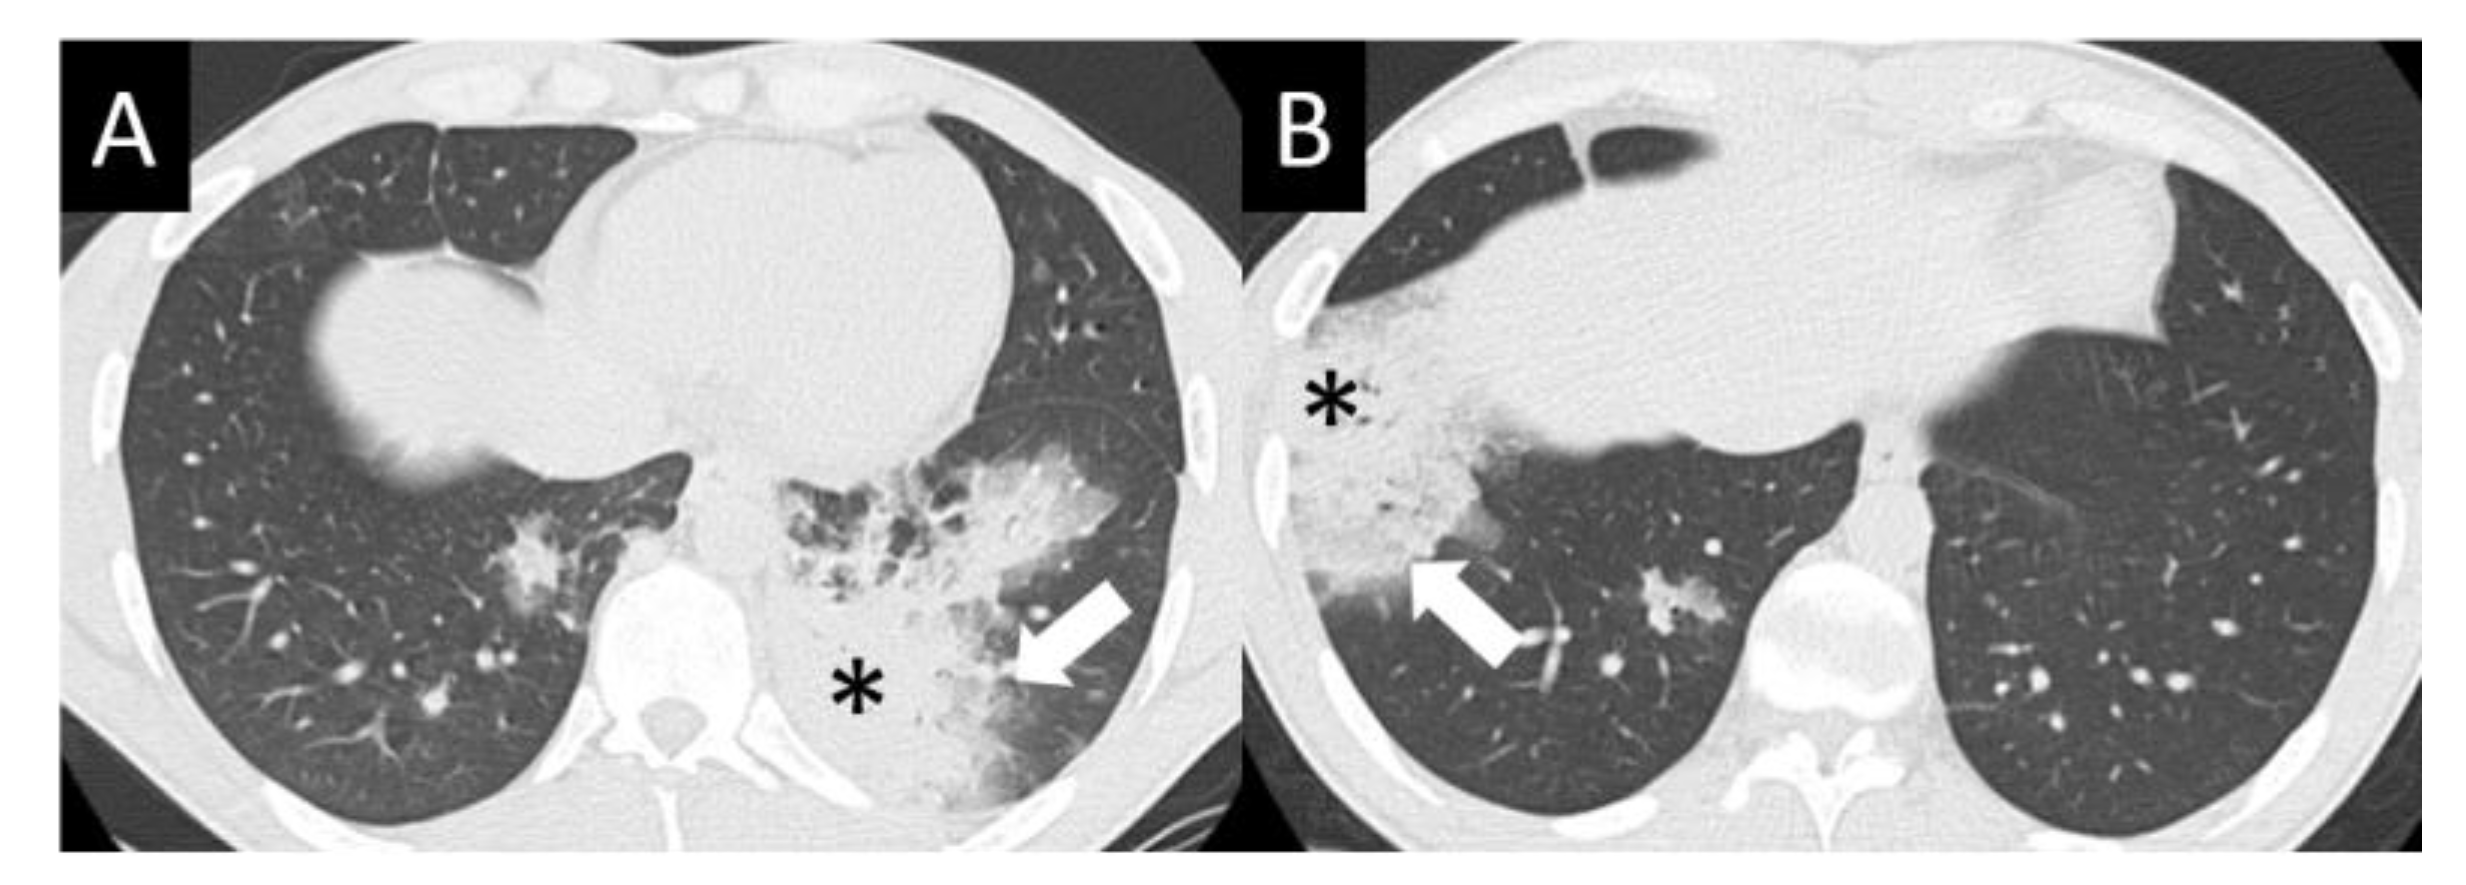

DAD is the most aggressive presentation and is usually present in grade 4 DI-ILD. Features of DAD on CT include ground glass opacities (GGOs) with associated areas of consolidative opacities (Figure 3). OP is characterized by multifocal areas of GGO and peripheral consolidation. Reversed halo/atoll signs may also be seen (Figure 4). NSIP is characterized by GGO, which tends to be basal with peripheral reticular opacities (Figure 5). Features of HP on CT include diffuse GGO, ill-defined centrilobular nodules, mosaic attenuation on inspiratory images, and air trapping on expiratory CT images (Figure 6).

Figure 4.

Organizing pneumonia (OP). OP is characterized by multifocal areas of peripheral consolidation (asterisks) and less dense areas of ground glass opacity (arrows). Reversed halo/atoll signs may be seen. OP often fluctuates. (A) Typical OP at baseline: Large volume of consolidation (asterisk), predominantly in the left lower lobe, and mild surrounding GGO (arrow). (B) Follow-up image 3 months later shows complete resolution of left lower lobe findings and new right lower lobe consolidation (asterisk) and GGO (arrow).